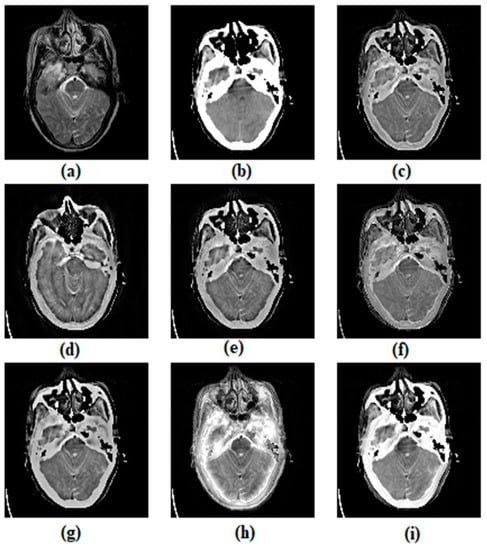

3.1. Subjective Assessment

| Metrics | Methods | ||||||

|---|---|---|---|---|---|---|---|

| ASR | CVT | DTCWT | MSVD | CSMCA | NSST | Proposed Method | |

| EI | 67.026 | 79.944 (2) | 75.086 | 64.169 | 70.435 | 75.318 | 80.087 (1) |

| MI | 4.279 | 3.904 | 4.030 | 4.227 | 4.346 (1) | 4.116 | 4.339 (2) |

| VIFF | 0.272 | 0.254 | 0.249 | 0.286 | 0.297 (2) | 0.241 | 0.356 (1) |

| 0.472 | 0.421 | 0.435 | 0.392 | 0.481 (1) | 0.421 | 0.480 (2) | |

| SSIM | 0.593 | 0.276 | 0.413 | 0.301 | 0.537 | 0.600 (1) | 0.599 (2) |

| AG | 6.662 | 7.887 (2) | 7.421 | 6.812 | 6.877 | 7.471 | 7.980 (1) |

| RMSE | 0.029 | 0.029 | 0.029 | 0.028 | 0.029 | 0.024 (2) | 0.021 (1) |

| PSNR | 16.857 | 17.171 | 17.720 | 15.804 | 17.892 (1) | 13.981 | 17.794 (2) |